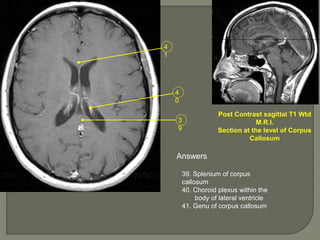

Post Contrast sagittal T1 Wtd

M.R.I.

Section at the level of Corpus

Callosum

Answers

39. Splenium of corpus

40. Choroid plexus within the

body of lateral ventricle

41. Genu of corpus callosum